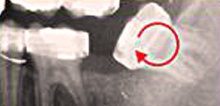

Diagnosis

State-of-the-art low-radiation digital radiography

Our X-ray technology now is so sophisticated, that the dose of radiation from one X-ray is less than a fifth of that from an overseas flight. Still, we reduce total exposure by only taking as few X-rays as are required and always protecting radiation-sensitive tissue areas.